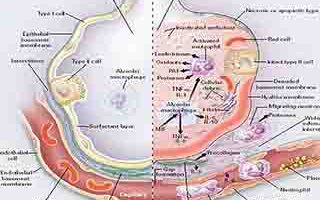

اسلاید 18: پاتوفیزیولوژی پاتوفیزیولوژی پایه پاسخ های ایمنی را می توان در سه فاز توضیف نمود : تخریب تحمل دهانی، حساس شدن به آلرژن و واکنش نسبت به آلرژن که منجر به ایجاد علائم آلرژی می گردد. سایر مکانیسم هایی که در حال بررسی می باشند شامل افزایش pH معده، فعالیت مستقیم مواد شیمیایی بیواکتیو، افزایش حساسیت عصبی- روده ای و اثرات اسمزی همراه با اتساع روده می باشند. نارسایی و یا ازدست دادن تحمل دهانی موجب حساس شدن به آلرژن ها می گردد.

اسلاید 19: زمانی که یک ماده غذایی یا مولکول قبلا بعنوان ایمن شناسایی نشده باشد، مرحله دوم، حساس شدن (sensitization) اتفاق می افتد که سلول های ایمنی در اولین مواجهه با آلرژن، به آن پاسخ نشان می هدند. این وقایع بوسیله پاسخ Th-2 و درگیری سلول های دندریتیک و اپی تلیال مشخص می گردد.مرحله سوم شامل واکنش مجدد به آلرژن در هر زمان که همان ماده خارجی یا آلرژن به بدن وارد می شود، می باشد و سلول های ایمنی با ترشح واسطه های التهابی یا مواد شیمیایی دفاعی باعث ایجاد علائم آلرژی می شوند.

اسلاید 45: مکانیسم این عملکرد ازطریق سلولهای T کمکی یا Th ها که TNF-alpha ترشح می کنند انجام می گیرد. در پاسخ Th1 ترشح TNF-alpha و سطوح پایین TGF-β که سایتوکاین درگیر در ایجاد تحمل به مواد غذایی می باشد، مشاهده می گردد و در نهایت منجر به عدم تحمل ایمونولوژیک و واکنش سیستم ایمنی بعنوان یک عامل تهدید کننده بیگانه نسبت به ماده غذایی می شود. همان طور که انتظار می رود، تست های IgE خاص آلرژن در تشخیص این اختلالات سودمند نمی باشد.